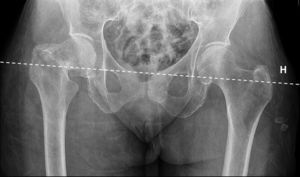

El plantillado acetabular comienza con el trazado de una línea horizontal de referencia para determinar la inclinación correcta del componente acetabular. En la gran mayoría de los casos puede trazarse esta línea a través de los vértices inferiores de ambas imágenes en lágrima28 (fig. 1). Si las imágenes en lágrima no fueran claramente visibles, pueden utilizarse los vértices inferiores de las articulaciones sacroilíacas. Los vértices inferiores de las tuberosidades isquiáticas están frecuentemente distorsionados por rotaciones pélvicas, fracturas previas o variaciones anatómicas.

Imagen radiográfica anteroposterior de pelvis que muestra una artroplastia total de cadera por fractura (paciente de la fig. 1) implantada tras la realización de la planificación preoperatoria (tabla 1). Se comprueba la correcta posición de los implantes y la restauración anatómica de la biomecánica de la cadera fracturada (centro de rotación, offset [O=O’] y longitud del miembro [d=d’]). d: distancia vertical desde la línea de referencia al ángulo proximal del trocánter menor de la cadera operada; d’: distancia normal; F: eje de la diáfisis femoral; H: línea de referencia horizontal entre ambas imágenes en lágrima; O: offset de la cadera operada; O’: offset normal; R: centro de rotación de la artroplastia; R’: centro de rotación de la cadera normal; Tm: trocánter menor.